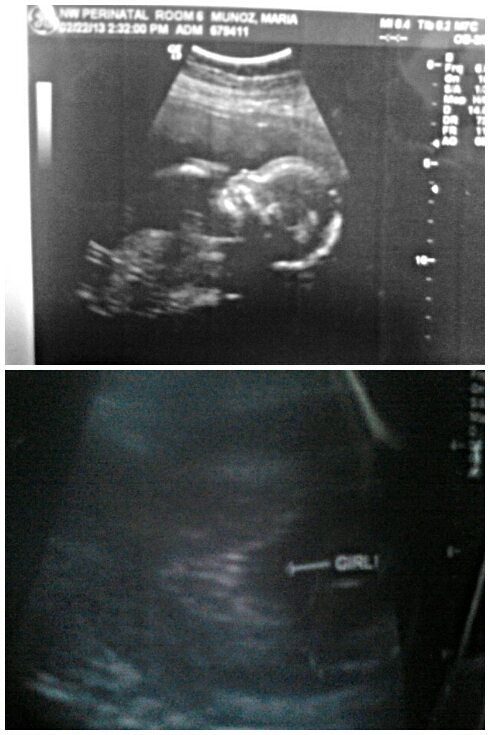

I got this scan done at 20 weeks, I already have a son so I was excited and extremely happy to hear this baby is going to be a girl, but I'm scared she is gonna turn out to be a he.... can anyone help me and tell me if this could still turn out to be a boy?Attachment 9250

Great hamburger shot...that's a girl!

That's what my girls looked like at 20 weeks. You can relax, there's nothing up front in that pic, and mine never sprouted boy bits after hamburger shots at 20 weeks along.

Definite GIRL 100% :cheer:

Attachment 9275